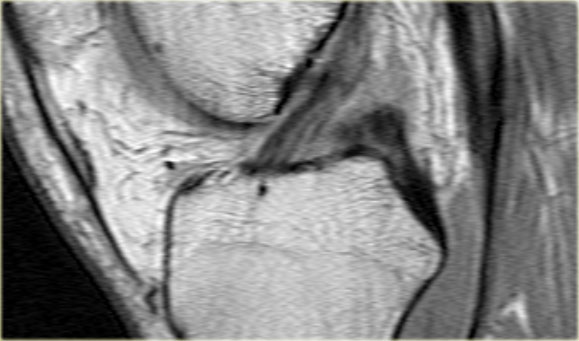

- Thân sụn chêm ngoài.

- Sừng sau quá nhỏ và sừng trước có vẻ to hơn với đường viền không đều.

- Thoạt nhìn có vẻ như có một đường rách dọc ở sừng trước, nhưng thực chất phần sau của cấu trúc này chính là phần lật của sừng sau bị rách.

Cấu trúc phía trước là sừng trước.

Cũng cần lưu ý tình trạng phù tủy xương khu trú và dấu ấn lõm sụn khớp. - Cấu trúc phía trước là sừng trước.

- Một số bất thường ở phần sau.

- Phần sau di chuyển về phía đuôi (caudal).

- Trong hố gian lồi cầu là điểm nối giữa mảnh di lệch và phần còn lại của sừng sau.